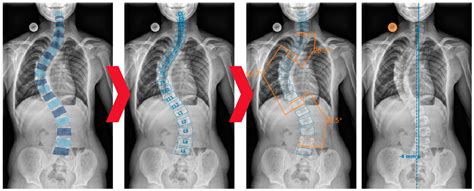

Measuring the Angle of Cobb

Measuring the Angle of Cobb involves several steps, typically performed using X-ray images. Here is a detailed guide on how to measure the Angle of Cobb:

1. Obtain a standing posteroanterior (PA) X-ray of the spine.

2. Identify the most tilted vertebrae above and below the apex of the curve.

3. Draw a line along the endplate of the most tilted vertebra above the apex.

4. Draw a line along the endplate of the most tilted vertebra below the apex.

5. Draw perpendicular lines to these endplate lines.

6. Measure the angle formed by the intersection of the perpendicular lines.

This angle is the Angle of Cobb and represents the degree of spinal curvature.

Monitoring Progression with the Angle of Cobb

Regular monitoring of the Angle of Cobb is essential for tracking the progression of scoliosis and adjusting treatment plans as needed. Healthcare providers typically recommend follow-up X-rays at intervals determined by the severity of the curvature and the patient’s age. For example:

• Mild curvatures may be monitored every 6 to 12 months.

• Moderate curvatures may require more frequent monitoring, such as every 3 to 6 months.

• Severe curvatures may need to be monitored every 3 to 4 months, especially in growing children.

By closely monitoring the Angle of Cobb, healthcare providers can intervene early if the curvature progresses, ensuring timely and effective treatment.